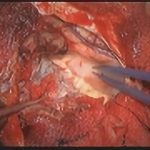

術中写真

摘出 前

摘出 中

摘出 後